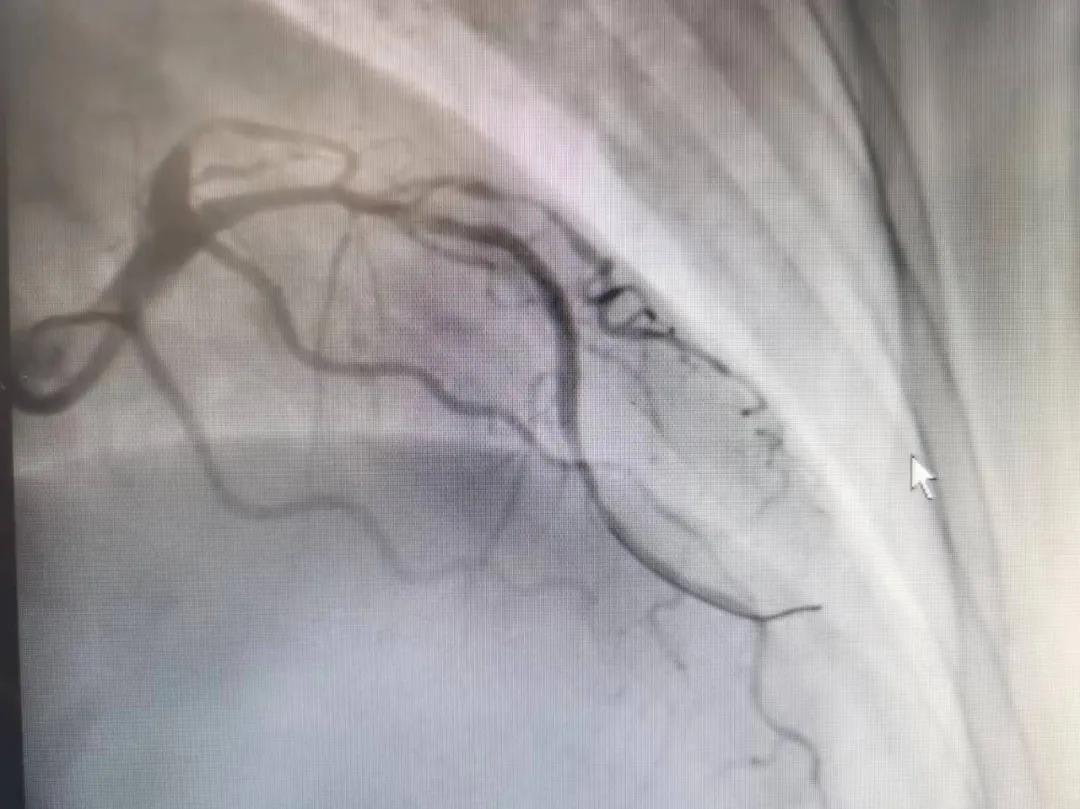

王瑾院長和李慧新主任帶領(lǐng)介入團(tuán)隊充分評估,決定行前降支冠狀動脈鈣化病變旋磨術(shù),術(shù)中應(yīng)用1.5mm旋磨頭,以15萬-17萬轉(zhuǎn)/分速度共對病變旋磨3次,累計旋磨時間60秒,后復(fù)查造影示鈣化明顯減輕,為后續(xù)操作創(chuàng)造了良好條件,隨后應(yīng)用預(yù)擴(kuò)張球囊、切割球囊再次處理病變,并順利植入支架1枚,復(fù)查造影顯示支架膨脹及貼壁良好,無夾層、血腫、慢血流等情況,手術(shù)順利完成?;颊咝g(shù)后無不適,胸悶、胸痛癥狀明顯緩解,順利出院。

術(shù)后